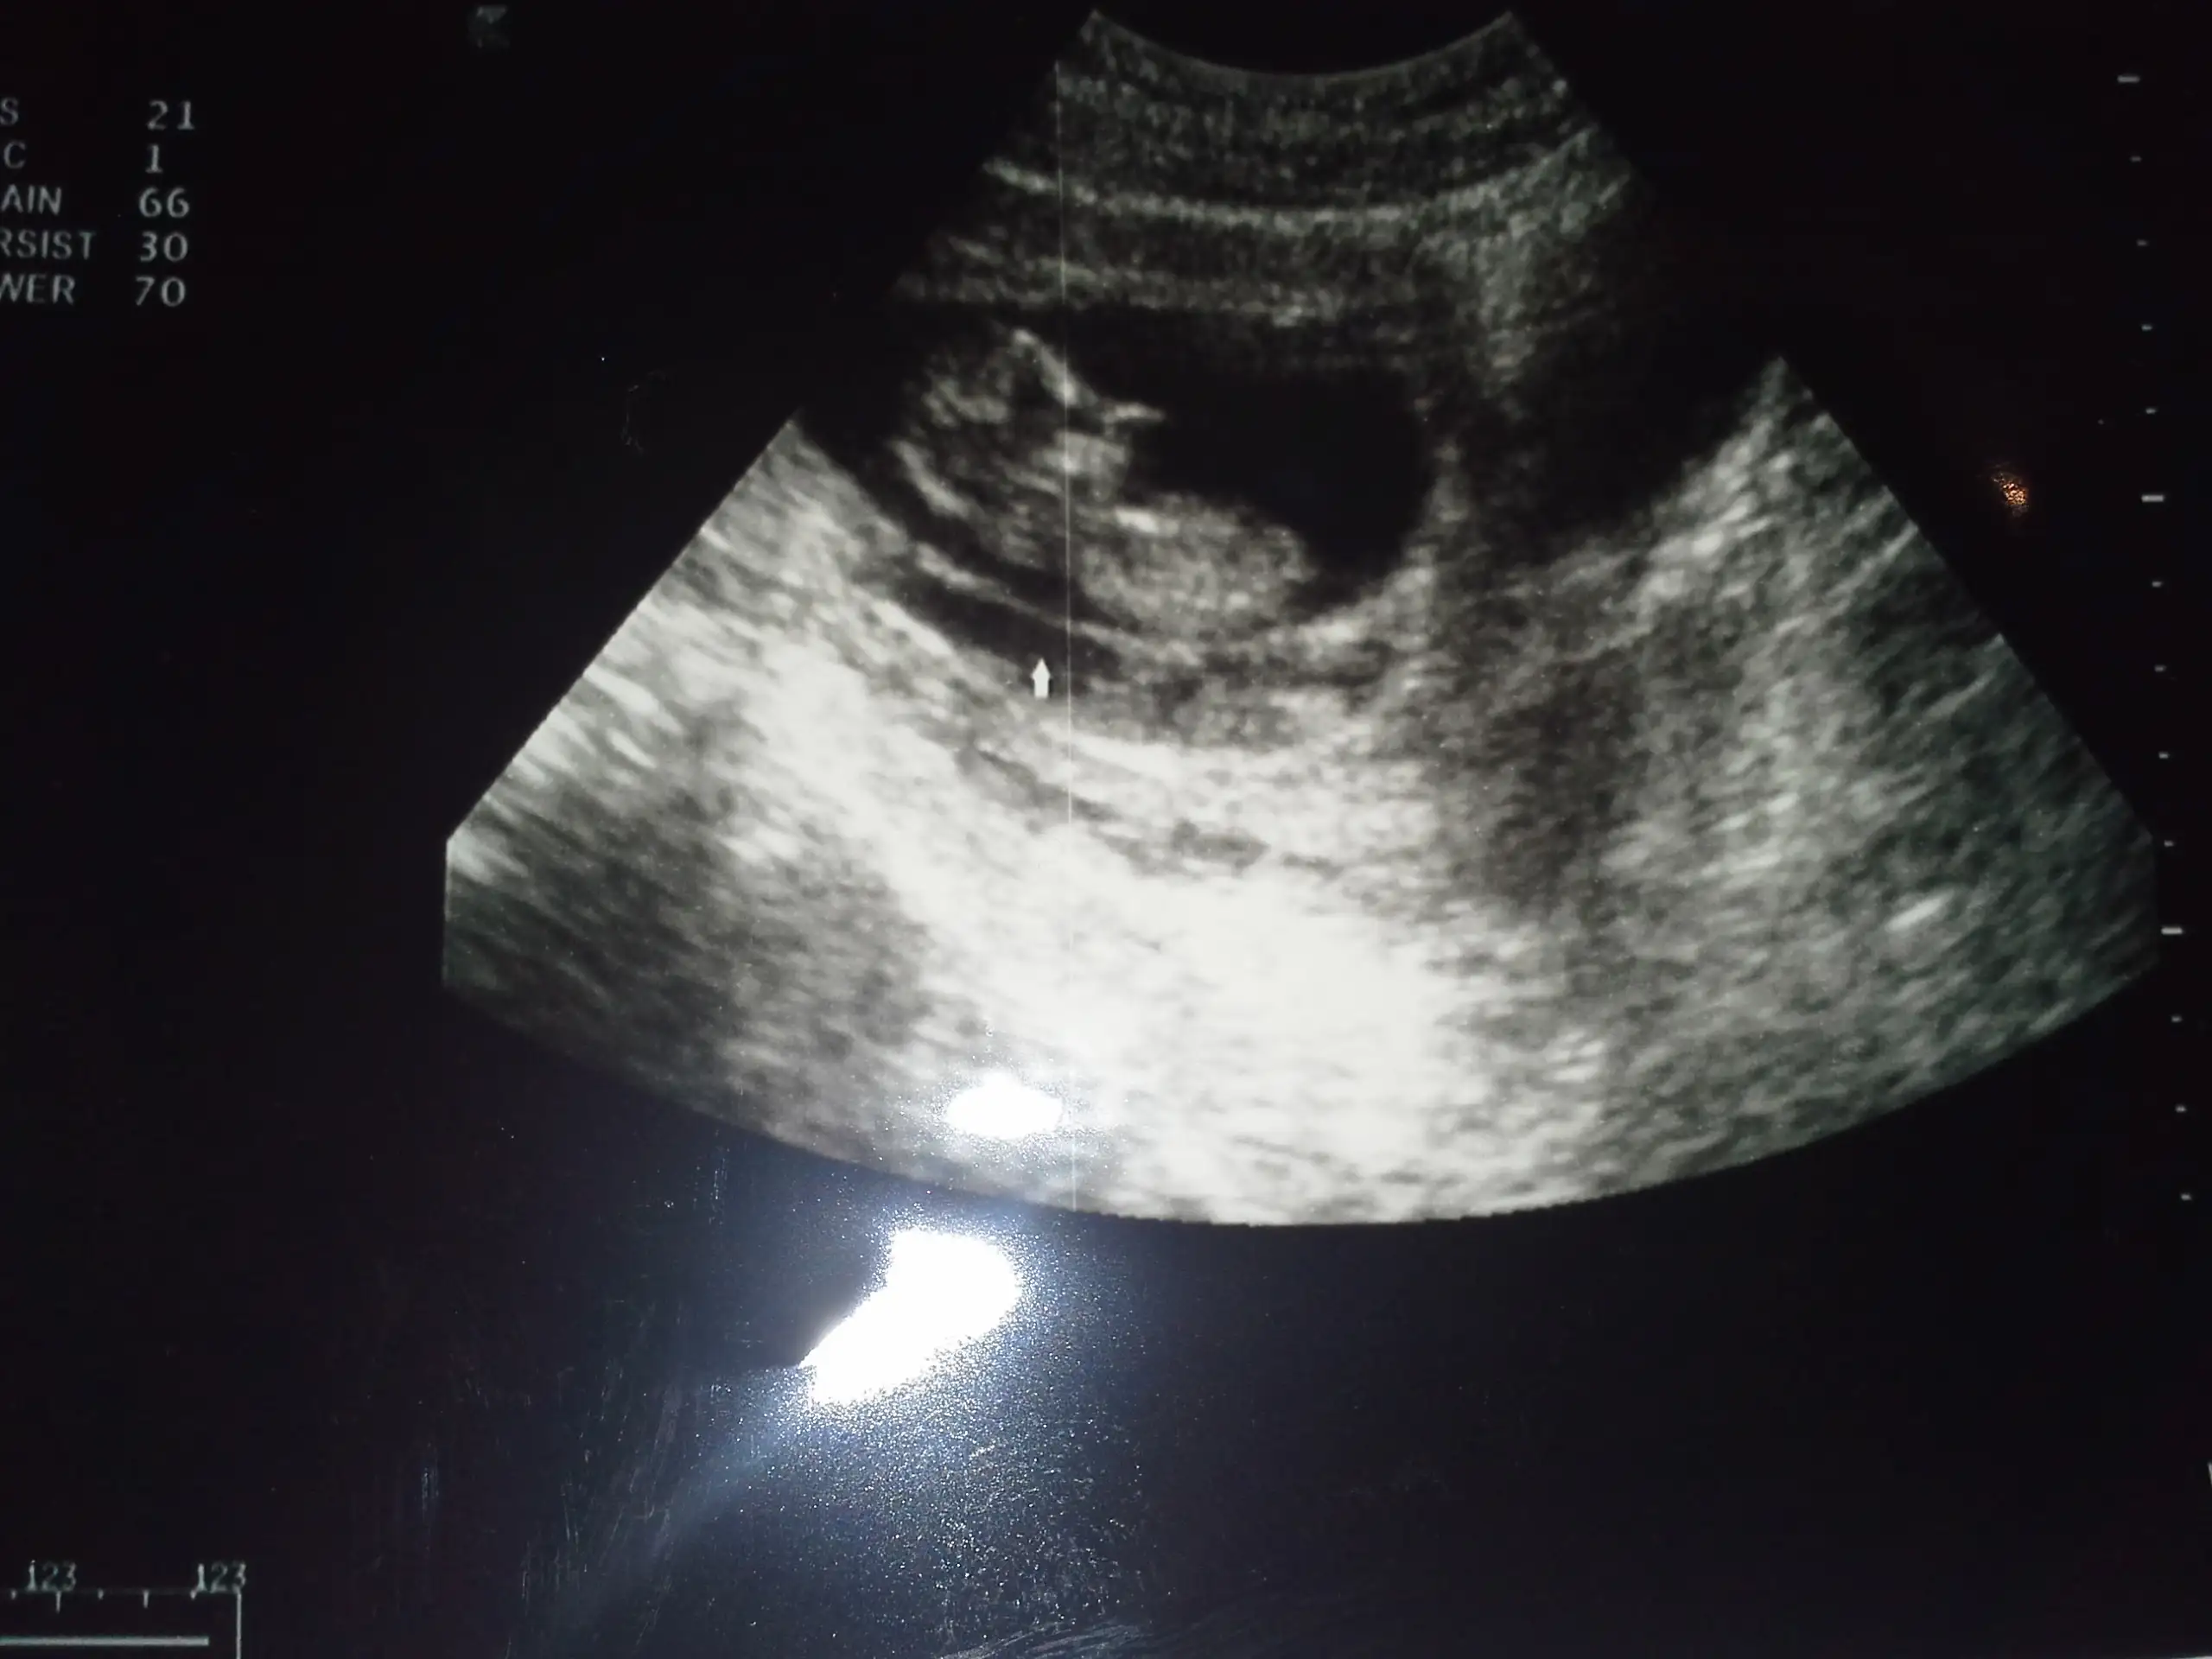

Eklentiler

• 20141030_190325.webp

20141030_190325.webp

105,7 KB · Görüntüleme: 145

canim kanama alani ne kadarmis?.. Ne dedi doktor.. Bende de vardi 2.5 cm.. Seninki daha kucuk gozuktu bana..

boyutunu söylemedi canım,çok dedi sadece.Bu ultrasom resminde kesenin yanındaki dimi,kesenin yarısı kadar galiba,resimden anlayamadım

,orda ekrandada görüntü çok gidip geliyordu